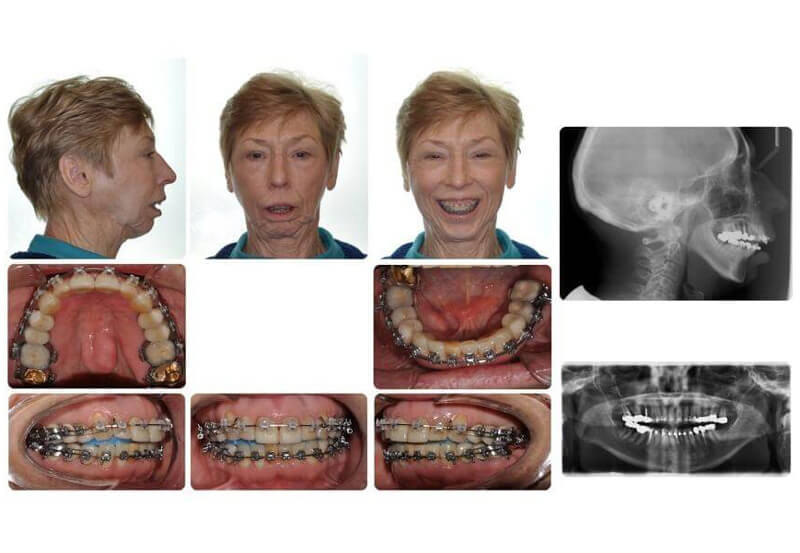

Case Report: